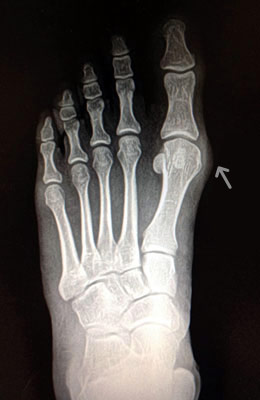

Before

Lapidus Forever Bunionectomy™ Before image

After

Lapidus Forever Bunionectomy™ after image

Lapidus Forever Bunionectomy™

Whitney, a 47-year-old businesswoman who could not fit into her dress shoes because of her bunion and terrible calluses caused by it. We performed a Lapidus Forever Bunionectomy™ on her big toes and she was able to bear weight on her foot 2 weeks after surgery and was back in her heels at 8 weeks post-surgery with no pain and now an amazing looking foot. After image was taken 12 weeks post-op.